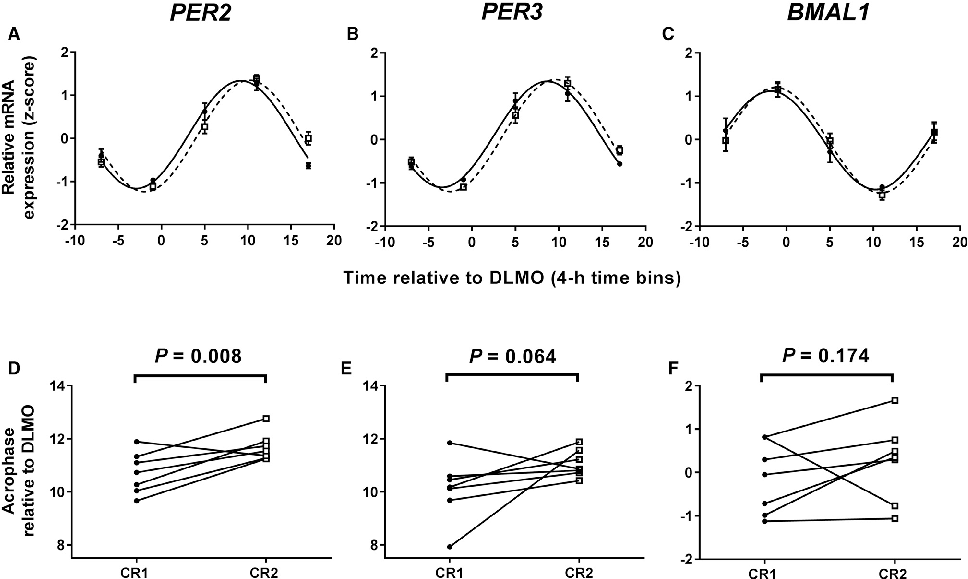

Clock gene expression patterns in adipose tissue are compared between the two meal timing conditions, revealing tissue-specific circadian phase shifts.

Meal Timing Regulates the Human Circadian System.

Per2 and other clock gene transcript levels measured from peripheral blood samples demonstrate delayed phase alignment consistent with the shifted meal schedule.

Meal Timing Regulates the Human Circadian System.